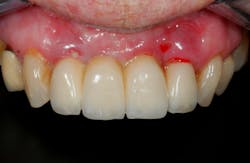

Late complications of bone augmentation are now recognized more frequently and include late resorption, foreign body reaction (figures 2a–2b), late breakdown of grafted sites (figures 3a–3e), lack of keratinized tissue and poor esthetics, as well as implant failure. While all bone augmentation procedures result in some degree of bone remodeling and resorption, significant late graft resorption can jeopardize the supporting bone around an already integrated implant, resulting in implant dehiscence, peri-implant disease, and late implant failure (figures 4a–4c). The degree of resorption depends on three important factors: alveolar defect configuration, patient factors, and the technique and grafting materials chosen.3

Figures 3a–3e: Socket preservation was performed at the site of the left mandibular second molar after extraction, using a biomaterial two years prior to implant placement. Six years after implant placement, sequestration of the biomaterial is seen, resulting in peri-implant infection and failure of the implant.